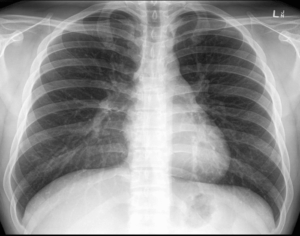

Видно ли рак легких на флюорографии или нет? Данный метод исследования не позволяет точно определить злокачественную опухоль, а позволяет лишь увидеть само новообразование. Врач делает снимки в прямой проекции. При необходимости делают боковые снимки, что позволяет определить какой именно рак:

Так показывает ли флюорография рак? Да, рентгеноскопия позволяет увидеть врачу рентгенологу затемнение или просветление, контуры, полости новообразования. Да и сам пациент может просмотреть рентген и увидеть, так как чаще всего четко просматриваются заболевания органов дыхания.

Рентгеноскопия характеризуется высокой степенью информативности и в 80% случаев позволяет обнаружить легочную онкологию. Лишь в малой доле случаев, рентгеноскопия отображает нормальное состояние легочных тканей при наличии онкологического процесса легочной системы.

При центральной форме ракового образования, на рентгенографии будет отображаться, что в легких присутствует расширенная сеть сосудов, а также имеются замутненные участки. Когда у легочной онкологии периферический характер, картина на рентгеновском изображении будет отображать присутствие четкой тени с неровными краями, от которой к корню легких отходят отростки в виде лент.

Как выглядит новообразование на флюорограмме?

Как выглядит рак легких на флюорографии? Конечно, опухоль на снимке сложно распознать неспециалисту. Квалифицированный доктор может ее заподозрить по следующим признакам:

- Наличие уплотнения. Чаще всего оно одностороннее, отбрасывает тень. К нему могут примыкать тяжи. При этом заметно, что корни легкого будут несколько расширенными.

- Тень, которую отбрасывает уплотнение, разной формы. Но чаще всего именно шаровидной. Как правило, она имеет нечеткие края, вокруг нее может быть некоторая «лучистость».